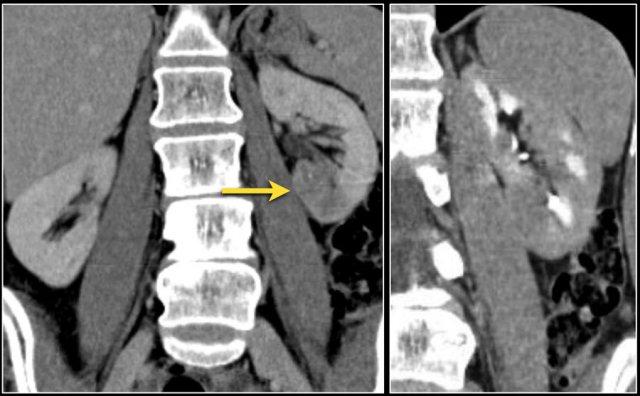

Giả u (Pseudotumor). Thì thận (Nephrogenic phase) ở bên trái và thì vỏ-tủy (Corticomedullary phase) ở bên phải.

Đây là một trường hợp khác.

Ở thì thận, có thể đặt ra nghi vấn về sự hiện diện của một tổn thương ở thận trái.

Tuy nhiên, ở thì vỏ-tủy, rõ ràng đây là một giả u (pseudotumor).